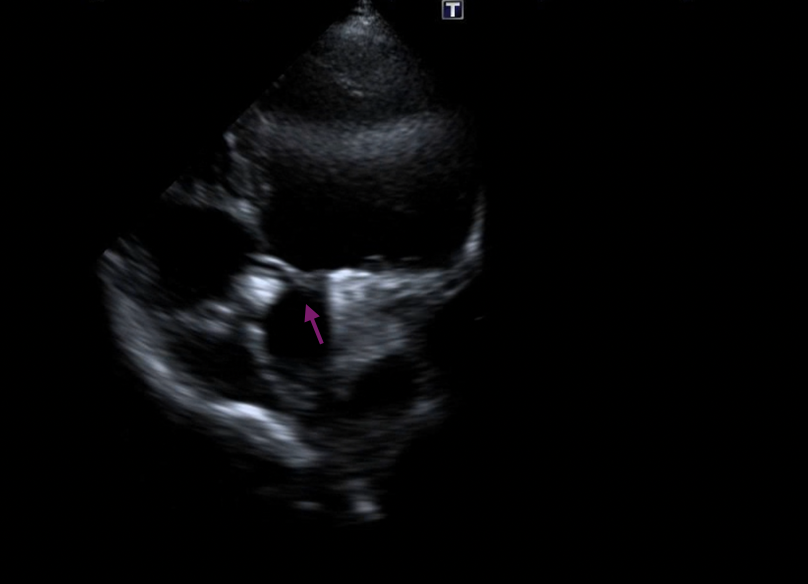

Gentle traction was exerted on the delivery cable to confirm seating of the left disc on the aortic side without slippage into the ruptured SVA. The rest of the occluder was deployed on the right side across the lesion (Figure 5A-B, Videos 5A-B).

Figure 5. (A) Device deployed (purple arrow). (B) Transthoracic echocardiography.

(Figure 5B)